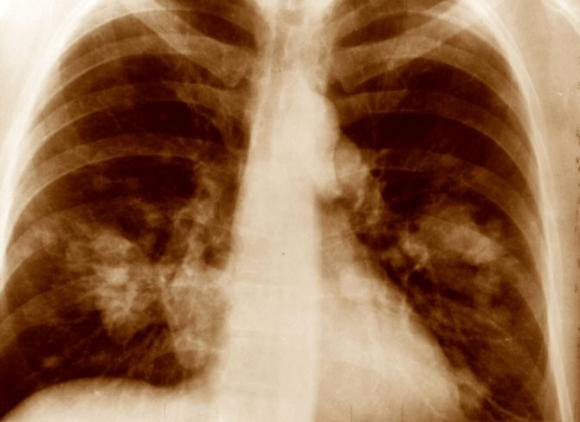

Para cientos de miles de personas, la lesión en un músculo causada por una operación de cirugía o por un accidente como por ejemplo caerse yendo en bicicleta, puede conducir a una inusual pero grave complicación: El crecimiento de tejido óseo donde debería crecer tejido muscular.

El descubrimiento, verificado en tejidos humanos y animales, identifica por tanto un objetivo molecular para fármacos. Un medicamento que actúe sobre la Sustancia P del modo apropiado, sería capaz de prevenir y tratar el crecimiento anormal de materia ósea, un proceso anómalo que se conoce como osificación heterotópica.

El equipo de Jack Kessler, Lixin Kan y Frederick Kaplan ha comprobado que la cantidad de Sustancia P es notablemente superior en los tejidos con daños recientes de pacientes que tienen la osificación heterotópica más común, así como en los casos provocados por una rara y severa enfermedad genética. En esta enfermedad genética, el tejido conectivo comienza a osificarse y se acaba convirtiendo en hueso.